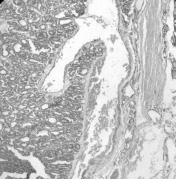

Рис. 3. Многофокусный рост папиллярного рака щитовидной железы. Окраска гематоксилином и эозином. X 100.

II.Многофокусный рост опухоли (мультицентричность). В отличие от фолликулярных карцином, многофокусный рост папиллярного рака встречался достаточно часто (рис. 3), особенно при неинкапсулированном раке смешанного (фолликулярном варианте папиллярного рака) строения. В случаях многофокусного роста папиллярных карцином чаще наблюдалось регионарное метастазирование.